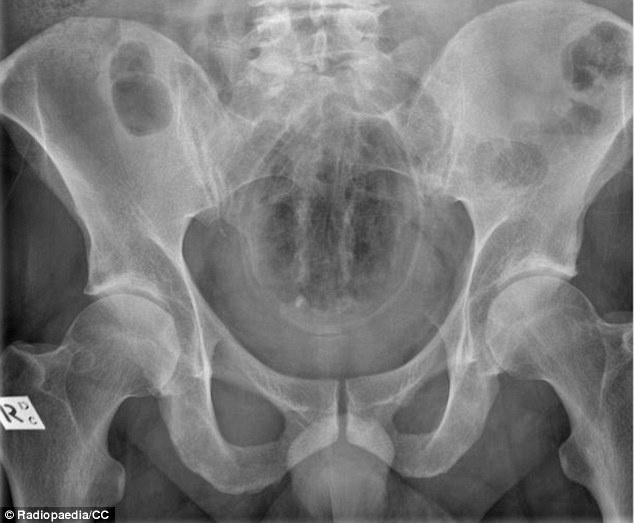

| Chiếc chày nhỏ chui vào trực tràng của một người đàn ông qua hậu môn khi anh đang nấu món ăn Malaysia. |